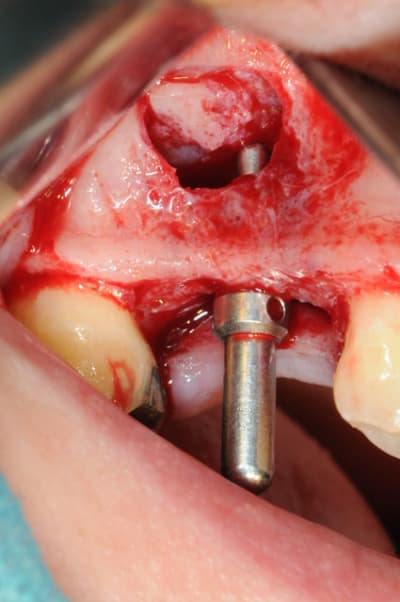

je sais pas si c'est un produit miracle, mais pour les sinus lift, c'est fantastique.

outre le fait de stabiliser un implant dans un sinus type SA4, pas de risque de voir partir le produit comme avec les granules de bioos et autres..

l'autre avantage est de ne pas avoir à mettre de membrane de recouvrement.

je suis donc hyper satisfait du résultat.

jugez plutôt...

l'application type du VitalOs, avec le bone splitting.

le protocole tel qu'il est d'écrit voudrait que l'on applique d'abord une couche de vital os en palatin - laisser durcir - mettre l'implant puis mettre une dernière couche.

ici, j'ai mis l'implant- maintenu la membrane de Schneider en poussant avec l'embout sur celle ci et terminer l'injection du produit. c'est l'un des avantages de ce produit, il est livré avec deux embouts donc les deux solutions sont possibles pour une même seringue.